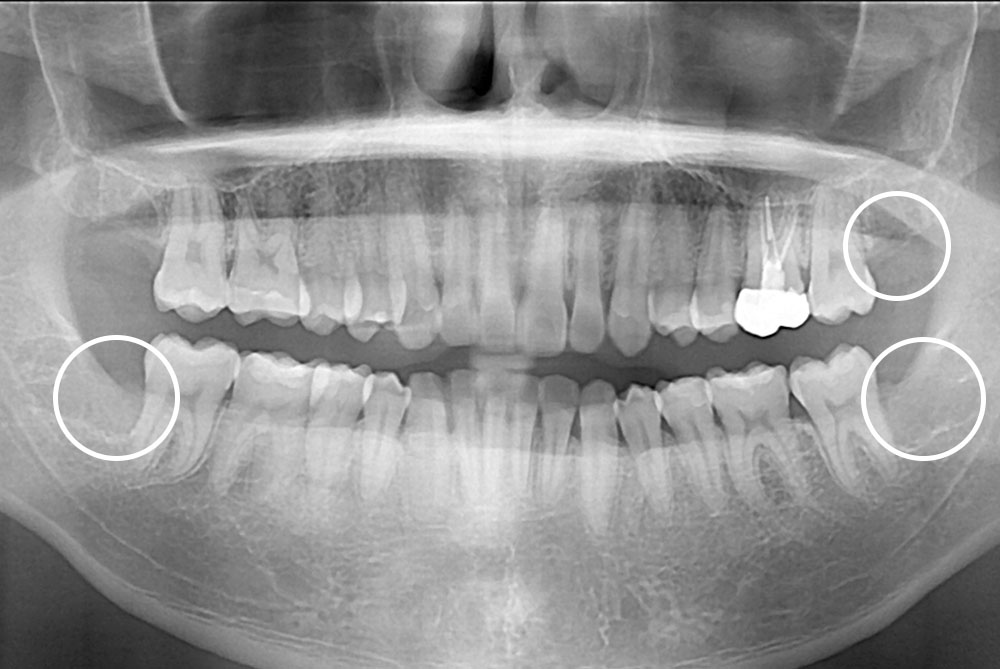

[사랑니] 매복 사랑니 발치

치료후 : 2019-08-28